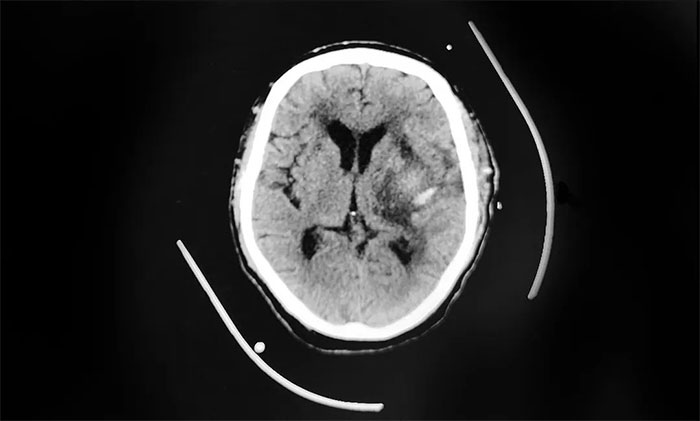

▲ 左侧基底节区出血